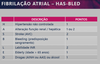

AVALIAÇÃO DO RISCO DE SANGRAMENTO NA FIBRILAÇÃO ATRIAL

CHADSVASC